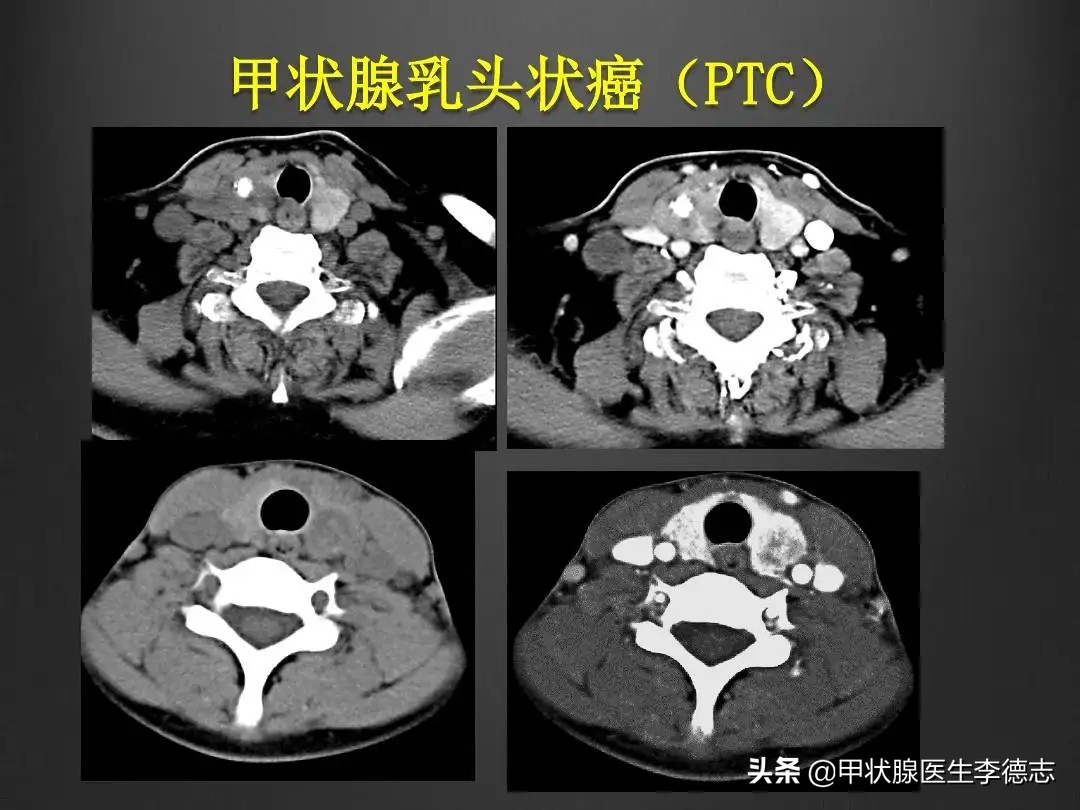

甲状腺乳头状癌

(PTC甲状腺乳头状癌)